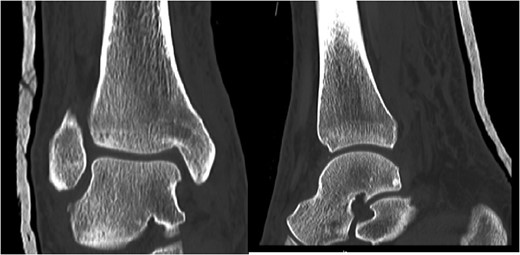

A 30-year-old male patient presented to Emergency Department (ED) following a run over injury. The patient described the mechanism of injury as moving his body over his run over foot. On clinical examination, there was obvious deformity and swelling of the right ankle. Dorsalis pedis pulse was felt but weak compared to the contralateral side with a capillary refill time under 3 s. The posterior tibial artery could not be palpated because of the deformity. X-rays showed posterior ankle dislocation without associated fractures (Fig. 1). Urgent reduction of the dislocation was done under sedation in ED. The knee was first flexed to relax the tendon Achilles then longitudinal traction with gentle forward force applied to the heel with immediate reduction of the deformity achieved. The foot was reassessed for vascular status. Triphasic pulse in both drosalis pedis and posterior tibial artery was detected with hand held Doppler. Ankle was immobilized in posterior below knee back slab to accommodate for swelling and check x-rays confirmed reduction of the ankle joint (Fig. 2). CT scan was done afterwards to define any subtle incongruity or osteochondral fragments entrapped in the joint. CT did not show any associated fractures and showed congruent reduction of the ankle joint (Fig. 3). Patient was mobilized touch weight bearing for first 2 weeks. The back slab was changed for weight bearing short leg cast and progressive weight bearing was allowed for the following 4 weeks. At 6 weeks follow up, plaster was removed and on examination patient still had moderate tenderness over the medial joint line and deltoid ligament area. Also, patient had limited range of plantar and dorsal flexion. Referral for physiotherapy was done for start of functional rehabilitation and range of motion exercises and in mean time MRI was done to delineate extent of ligamentous injury. MRI showed bone bruising of the lateral malleolus, medial malleolus and lateral talus (Fig. 4). The anterior talufibular ligament (ATFL), calcaneofibular ligament (CFL), posterior talofibular ligament (PTFL) and deltoid ligaments were sprained but intact. At 12 weeks follow up, patient could walk normally without any symptoms of instability and achieved 20° of both plantar and dorsal flexion. At 16 weeks, patient achieved full range of motion of ankle and was able to return to work. At 24 weeks follow up patient was able to resume his sport activates as preinjury level.

Post reduction CT scan showing congruent reduction of the dislocation without associated fractures.